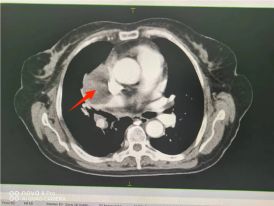

(四)肺癌

行IMRT治疗半程CT图像对比图